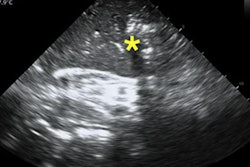

Researchers created a custom program that enhances the visualization of liver tumor blood vessels on CEUS scans. A model using features from the processed images accurately predicted which patients with hepatocellular carcinoma responded to one type of chemoembolization treatment. If validated, the software and model could help personalize cancer care. Read more in our Insider Exclusive.